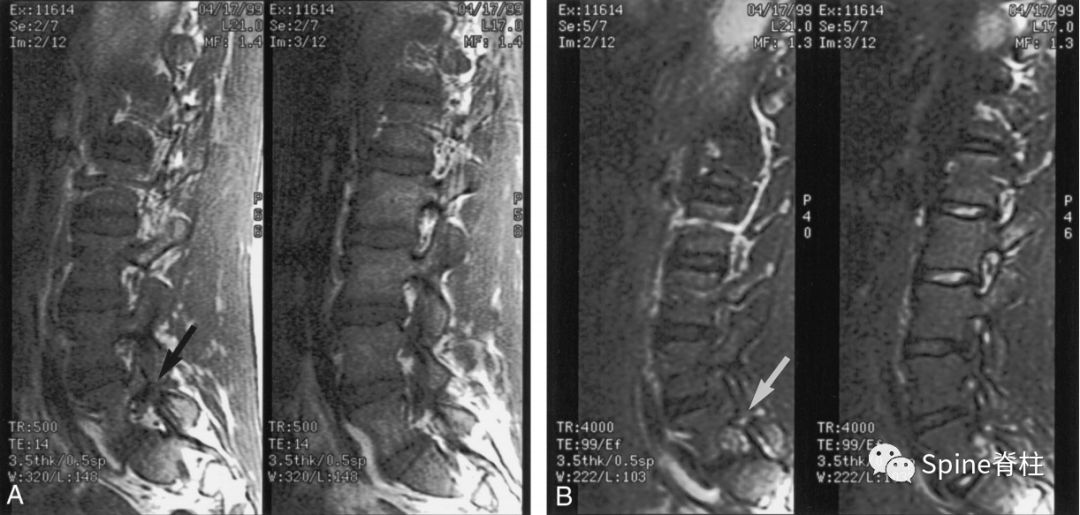

16岁的足球运动员诉右腰部疼痛。A:右侧T1加权像可见腰5峡部和椎弓根呈低信号(箭头);B:右侧T2加权像可见腰5峡部、椎弓根和关节突呈高信号(箭头)。

17岁的篮球运动员诉腰痛。A:T1像,左侧腰3峡部呈不连续的低信号(箭头);B:T2像,左侧腰3椎弓根和峡部呈高信号(箭头)

16岁的足球运动员,诉腰痛,以左侧为重。A:T1像可见腰5左侧峡部完全断裂(箭头);B:T2像,腰5左侧峡部、椎弓根和关节突水肿信号(箭头)

13岁运动员,左侧腰骶部疼痛。A:T1像,左侧腰5峡部完全断裂(箭头);B:T2像,左侧腰5峡部清晰可见,骨质无信号改变,峡部缺损处可见轻微的高信号,提示可能为肉芽组织或积液